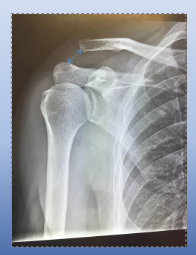

what is this an x-ray of?

acromioclavicular dislocation

acromioclavicular dislocation definition

clavicle separates from the scapula (acromion)

acromioclavicular dislocation cause

traumatic

radiographic appearance of acromioclavicular dislocation

widening of AC joint

technical change for acromioclavicular dislocation

no manual exposure factor change